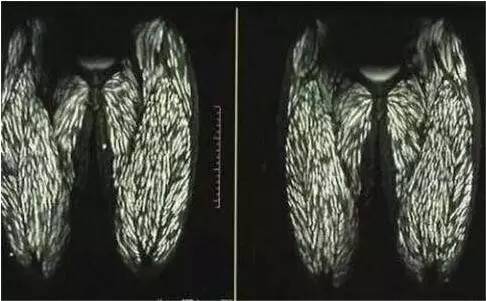

就因为这样的宠爱,可把小男孩给害了,这天小男孩突然肚子疼痛倒地难忍,还伴有呕吐症状,父亲立刻开车送医院,照了CT后医生却给他下了病危通知书。因为从CT上看小男孩身上都是寄生虫,医生诊断这些白色物体全是寄生虫,而且浑身上下全部都是。

就连腿部都是,看着这密密麻麻的寄生虫真的是在太恐惧了,估计密集恐惧症都犯了几十次了。